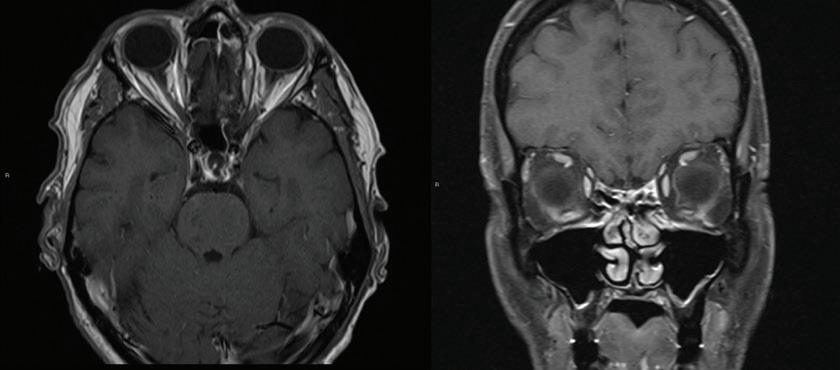

Eagle syndrome: Transient ischemic attack and subsequent carotid dissection

A 62-year-old man initially presented to our institution 3 months before his final diagnosis with transient right-sided weakness and brief loss of consciousness after reaching across his body in the shower. His medical history was significant for hypertrophic cardiomyopathy and atrial fibrillation. He had an implantable cardiac device and was on lifelong anticoagulation. Head computed tomography (CT) and CT angiography (CTA) were unremarkable, and although a transient ischemic attack (TIA) was thought to be unlikely given the anticoagulation therapy, this was a working diagnosis based on his symptoms, which were otherwise unexplained, and he was sent home.

The patient returned 3 months later with sudden-onset behavioral changes, disorganized speech, and right-sided weakness. He reported no specific activity related to symptoms. CTA demonstrated complete left internal carotid occlusion at the level of the styloid tip, 1-cm cranial to the bifurcation, which extended to the carotid terminus (figure 1). Review of imaging obtained at his presentation 3 months earlier demonstrated a normal carotid.

CT of the head obtained at the most recent visit demonstrated new anterior, middle, and posterior circulation infarcts. In addition, we observed not only that his left styloid process was elongated (3.0 cm), but also that his stylohyoid ligament was calcified to the hyoid and possibly fractured (figure 2). We speculate that the fracture might have acted as a lead-point, causing injury

and subsequent dissection of the patient’s carotid. The contralateral styloid process was within normal limits, but the ligament was also calcified.

Prophylactic contralateral styloidectomy was considered, but the patient was deemed a poor surgical candidate given his underlying cardiomyopathy and anticoagulation. After further review of imaging, we felt his right carotid was a safe distance from the right styloid and ligament. As the left carotid was occluded to the skull base, he was not offered revascularization. We speculate that our patient’s initial presentation

A B

Figure 1. A: 3-D reconstruction of the patient’s CTA with soft-tissue subtraction demonstrates the elongated and calcified stylohyoid ligament and dissected carotid artery cranial to the ligament (arrow). B: Additional 3-D reconstruction of the CTA with bone and soft tissue removed further demonstrates the dissected left internal carotid artery (arrow).

might have been a harbinger of his impending cerebrovascular accident.

Eagle Syndrome is an uncommon but well-described entity with a nonspecific clinical presentation; more benign manifestations include globus sensation, dysphagia, facial neuralgias, throat pain, and cranial neuropathies, for which a differential is extensive.1,2 In the presence of an elongated styloid bone or stylohyoid, diagnostic consideration is often given to Eagle syndrome, but it may have a more insidious presentation. Elongation of the styloid also has been reported as a cause for symptomatic carotid disease, including TIA, Horner syndrome, eye pain, and cluster headache.3 Dissection associated with elongated styloids has been reported in the neurology literature,4 but to the best of our knowledge, no prior reports have demonstrated TIA with a normal carotid and subsequent carotid dissection during two separate clinical presentations.

Surgical and nonsurgical treatments for Eagle syndrome have been reported. Medical treatments, including carbamazepine, local and systemic steroids, and NSAIDS have been used.4 Surgical options include transpharyngeal resection, as originally favored by Eagle, versus an extraoral resection.

Figure 2. A spherical cholesteatoma sac is discovered during surgical exploration. Figure 2. Axial CT shows the dissected internal carotid artery (arrow) and calcified stylohyoid ligament (asterisk).